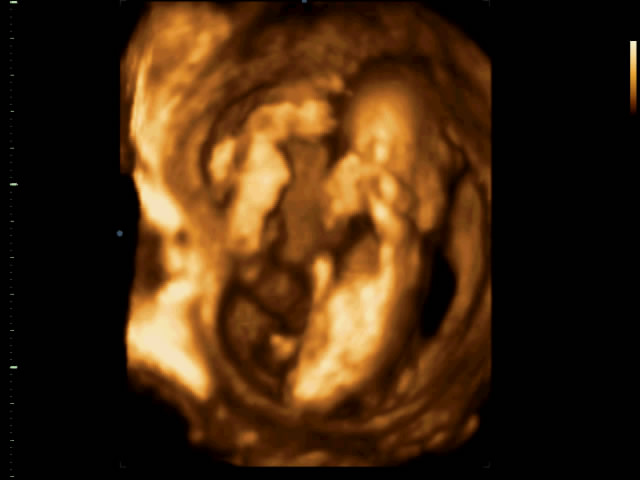

ElenaM_agrosvit@i.ua → Новенькая Спам Мама девочки (18 лет) Харьков Привет!!! Как вы думаете мальчик или девочка?

ElenaM_agrosvit@i.ua → Новенькая Спам Мама девочки (18 лет) Харьков Привет! Узи 14 недель сказали девочка. Что тогда это может быть между ног у моей девочки?